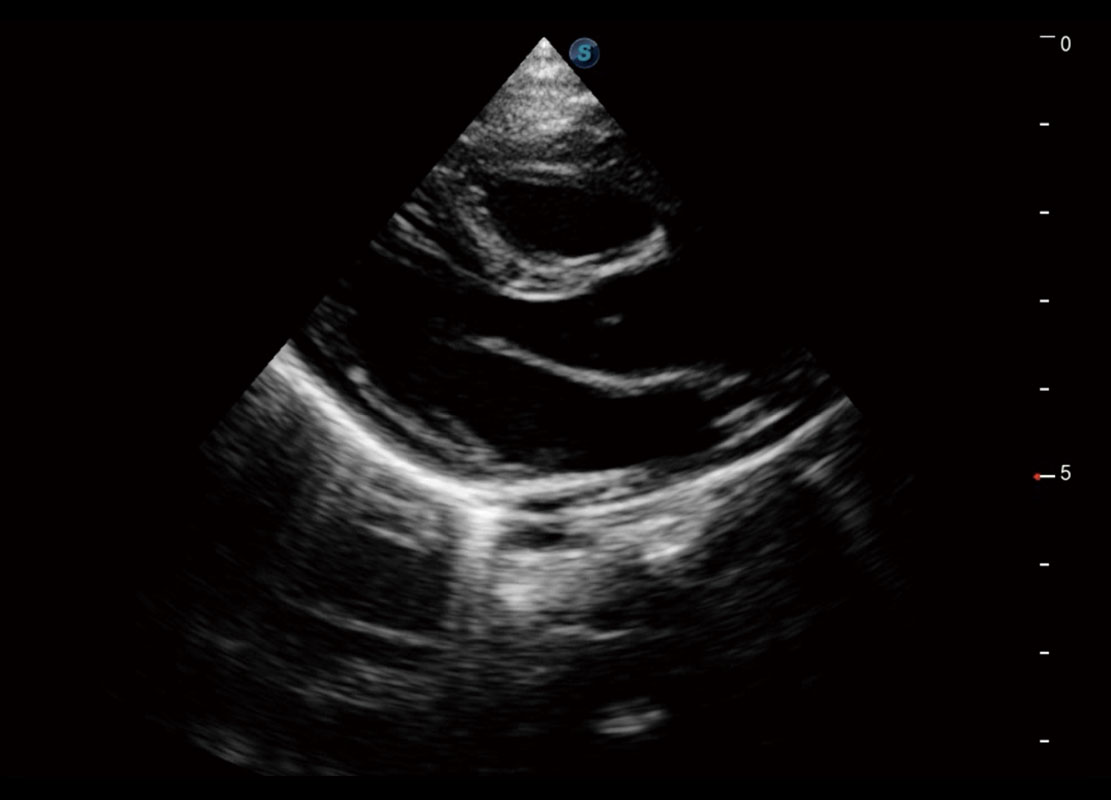

腔内三维-宫内节育器

腔内三维-光影成像